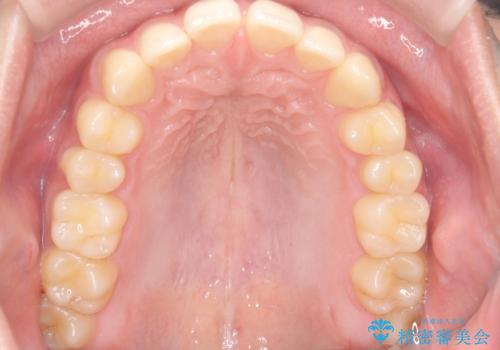

【ワイヤー矯正】すきっ歯を治したい

- 主訴:上の前歯のすきっ歯を治したい。

今回のような空隙歯列に対したは、マウスピース矯正・ワイヤー矯正どちらの方法でも矯正治療可能と説明し、ワイヤー矯正を希望されました。

上顎中切歯間の隙間の他にもフロスが抵抗なく入るスペースが上顎は数か所ありました。スペースを閉じ下顎の歯列弓との調和をとるためIPRを行いました。

下顎の舌側傾斜気味の前歯も唇側へ歯軸傾斜させています。

矯正期間:1年2か月